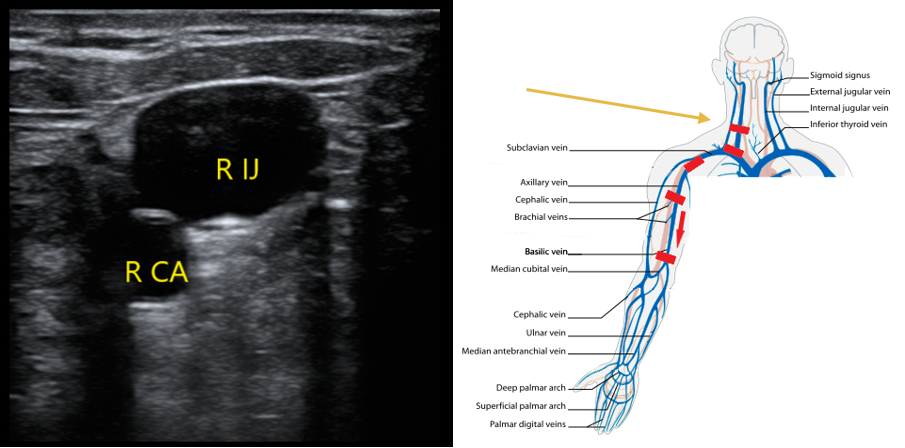

- Upper Extremity Scanning Protocol

- Start in the neck to evaluate the internal jugular vein to the level of the brachiocephalic. With the patient’s head turned to the contralateral side, place the transducer in a transverse orientation over the sternocleidomastoid muscle. You should be able to identify the IJ over the carotid artery (CA) (Fig. 3). Compress if you do not see echogenic material in the lumen of the IJ.

- Figure 3. Appearance of right internal jugular and right CA. Most caudal red rectangle indicates orientation of transducer.